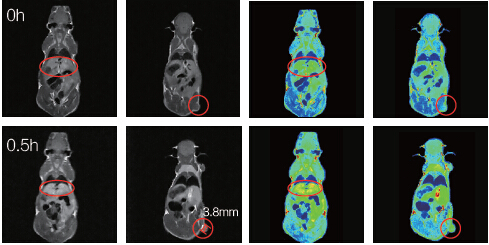

The mouse tumour measured 3.8 mm in diameter. Half an hour after administration of a novel Mn-chelate contrast agent, analysis of average grayscale values revealed significant contrast enhancement in both the liver and the tumour.